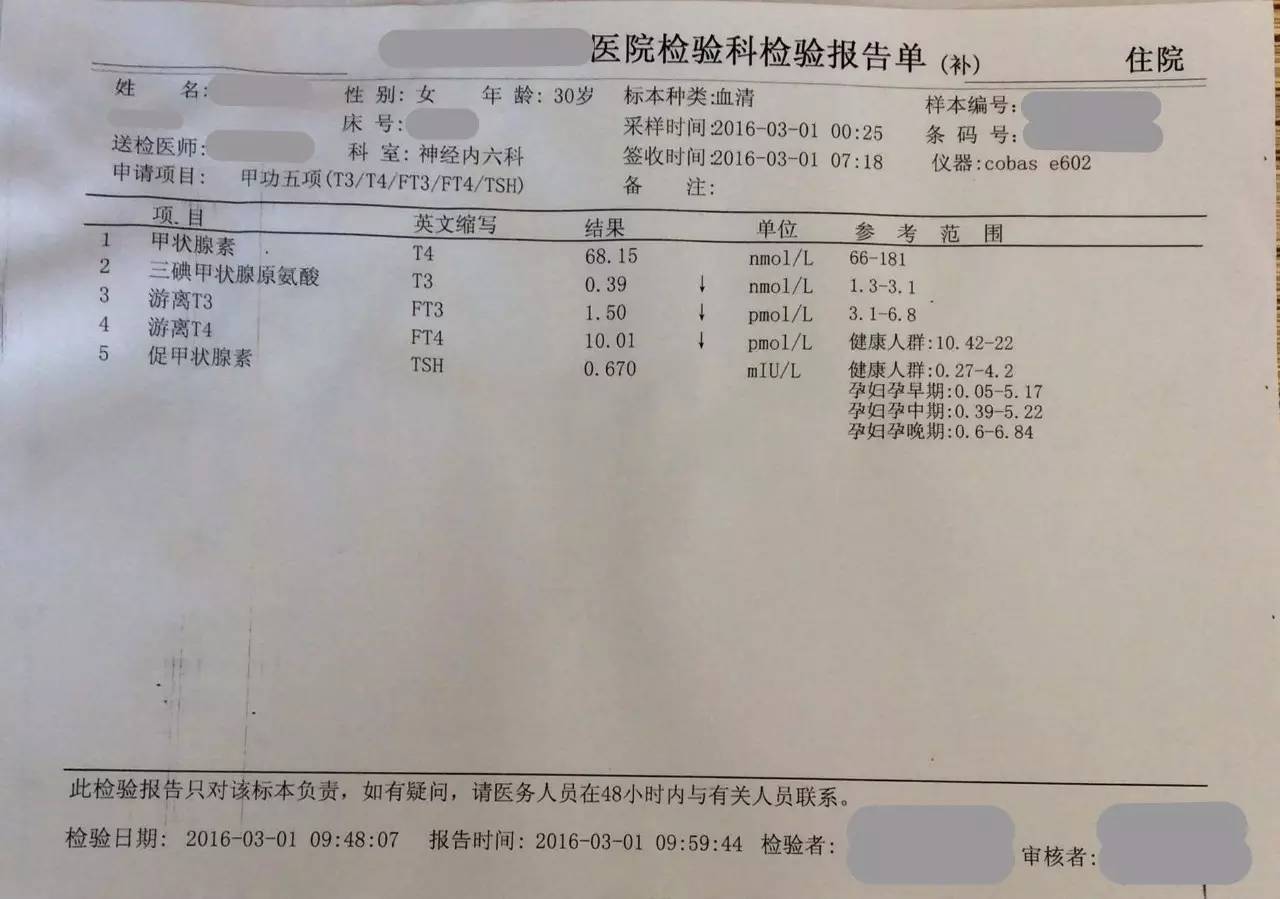

▼患者检查报告资料

1.甲状腺功能减退症:因为患者属于继发性甲状腺功能减退症,因此根据FT4水平来调整优甲乐的剂量即可,目前加量到100μg/天,同意这种调整;